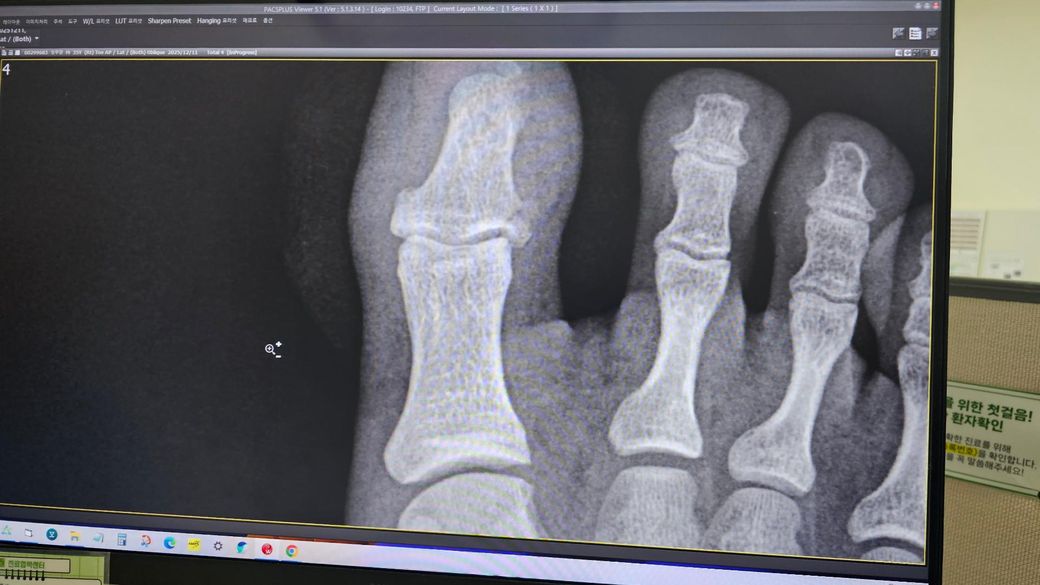

• 1번 째 사진

12월 11일밤 원판 20kg가 엄지발가락에 떨어져서 응급실 내방 개방성골절을 확인했고 후

12월 12일 금요일 오전 전문병원에서 핀을 박고 발톱 부위를 꿰맸습니다.